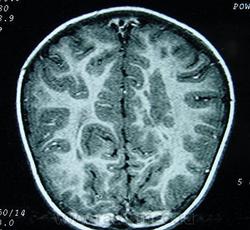

Гетеротопии. Перивентрикулярная гетеротопия. Субэпендимальная нодулярная (узелковая) гетеротопия.

Наиболее частым вариантом миграционных нарушений является гетеротопия - скопление нейронов, остановившихся в различных аномальных местах на пути следования к коре головного мозга. Такая остановка происходит не позже 5-го месяца внутриутробного развития. Изолированный участок узловатой массы называется «гетеротопион». В настоящее время описаны следующие варианты гетеротопии:

Перивентрикулярная субэпендимальная гетеротопия